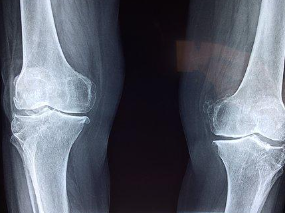

무릎통증 원인 3. 골관절염

골관절염은 노화로 인한 연골의 파괴로 발생하는 질환으로 무릎통증을 일으키는 대표적인 원인 중 하나입니다. 골관절염은 연령이든 성별이든 누구에게나 일어날 수 있으며, 무릎관절의 통증 뿐만 아니라, 염증으로 인한 열감, 붓기 등의 증상을 동반합니다.